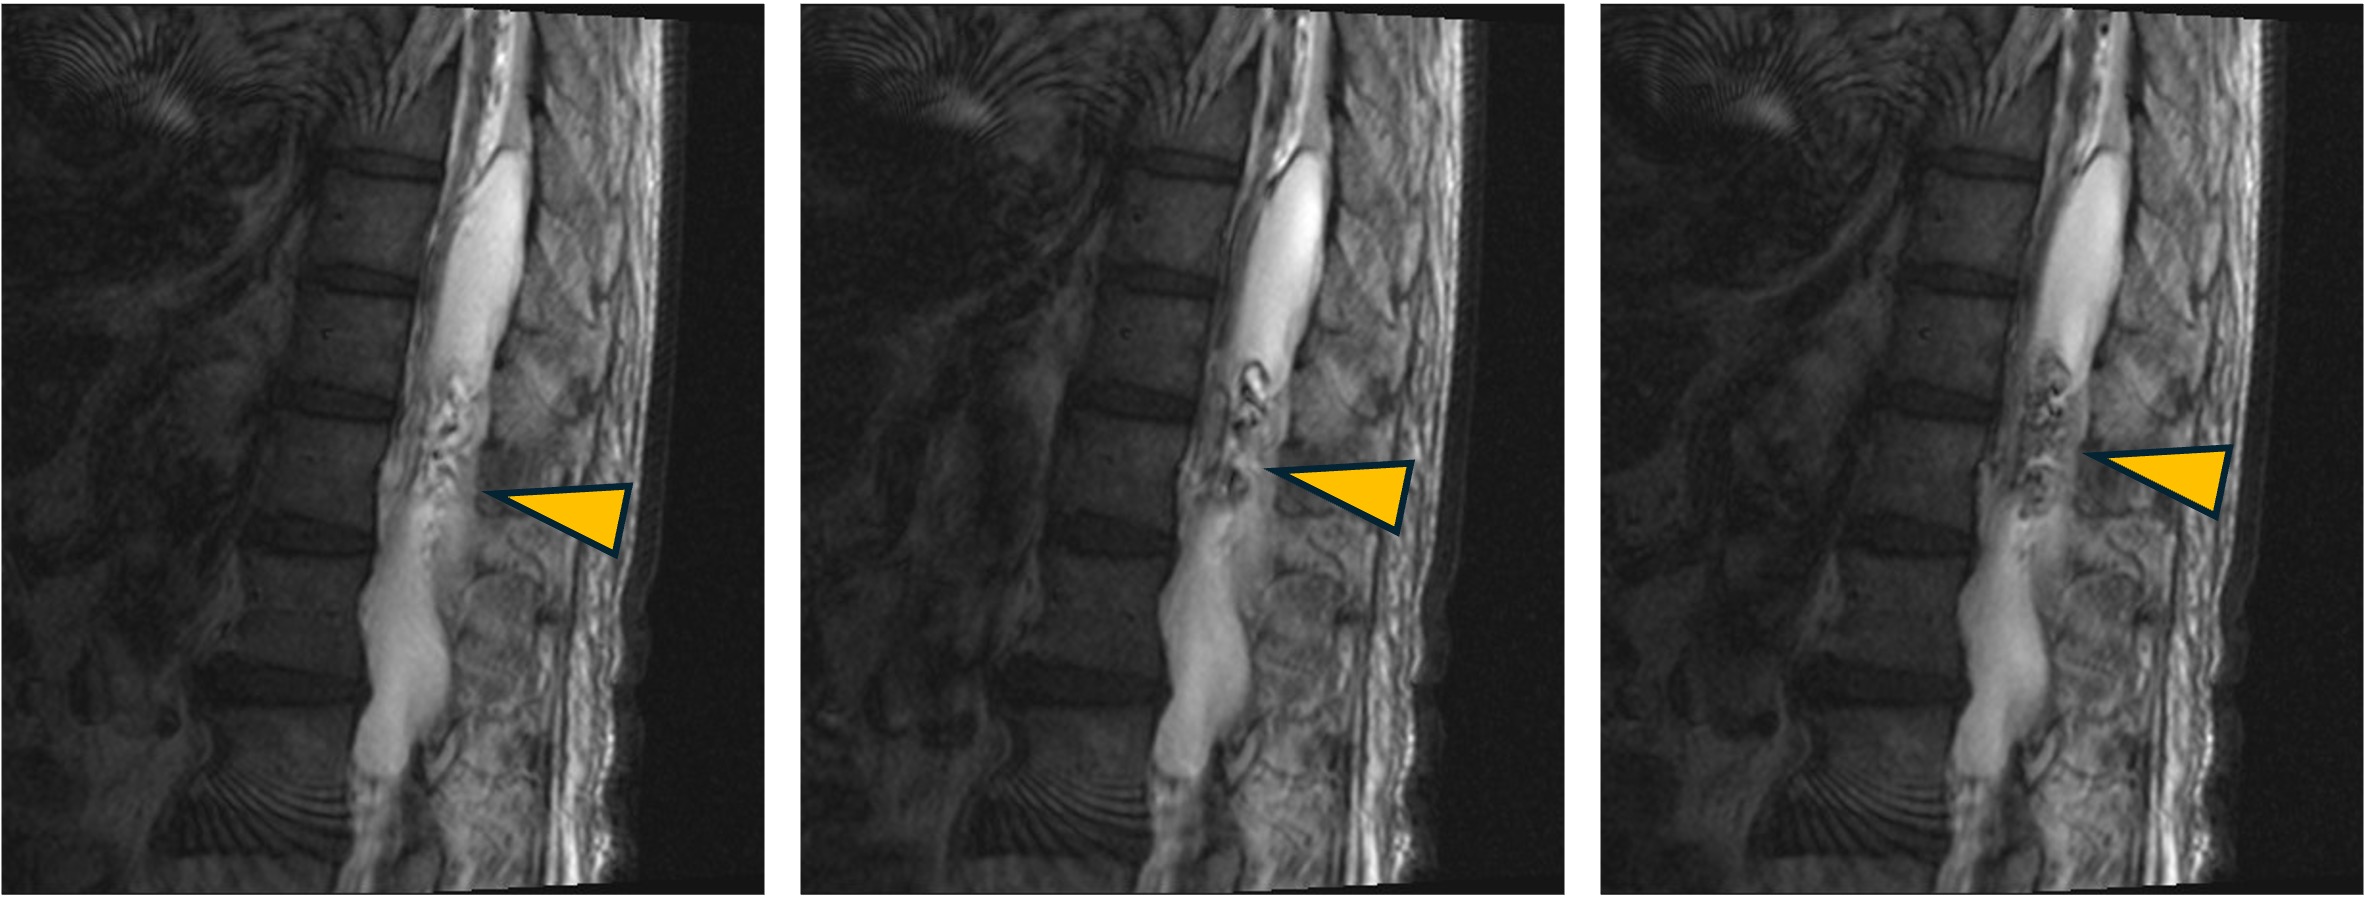

症例:CSF-flowの描出

PSIF-CINE imagingによるCSF flow症例。

第3脳室〜第4脳室にかけての髄液の拍動性流動が明瞭に確認できます。